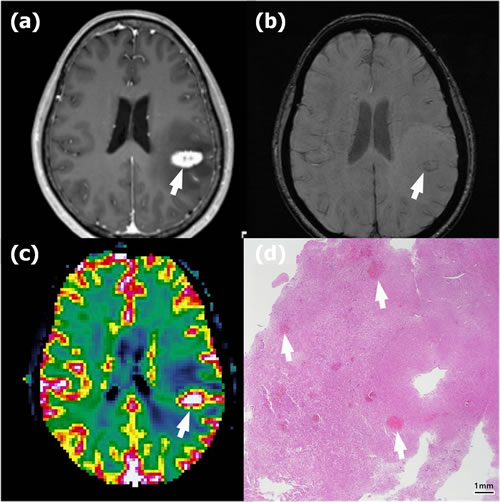

Figure 3: Recurrence in a 58-year-old woman with anaplastic astrocytoma in the left parietal lobe who underwent gross total resection and concomitant chemoradiotherapy (CCRT) with temozolomide. a. Contrast-enhanced T1-weighted (CET1) magnetic resonance (MR) image obtained 14 months after CCRT completion shows a newly appearing enhancing lesion in the left parietal lobe (arrow). b. Susceptibility-weighted imaging demonstrates nearly no dark area in the corresponding lesion (arrow); the proportion of dark signal intensity was 0.30 %. c. The normalized relative cerebral blood volume map (nCBV) from dynamic susceptibility contrast perfusion-weighted imaging shows increased blood flow in the corresponding enhancing area (arrow) (calculated 90th percentile points in the cumulative nCBV histogram (nCBV90) = 5.13). d. Hematoxylin-eosin-stained histopathology (original magnification, X 10) shows multiple hemorrhages of ≤ 5 mm (arrows) within the recurrent anaplastic astrocytoma.